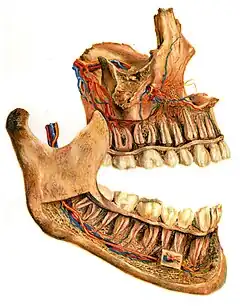

![]() Human jaws with anterior (frontal) portion of alveolar processes cut away towards right | |

On the maxilla, the alveolar process is a ridge on the inferior surface, making up the thickest part of the bone. On the mandible it is a ridge on the superior surface. The structures hold the teeth and are encased by gums as part of the oral cavity.[11] Congruent with much of the mandibular canal, the alveolar process comprises cells, nerves, blood vessels, lymphatic vessels, and periosteum.[8] The alveolar crest terminates uniformly at about the neck of the teeth (within about 1 to 2 mm in a healthy specimen).[12][13]

The alveolar process proper encases the tooth sockets, and contains a lining of compact bone around the roots of the teeth, called the lamina dura.[8] This is attached by the periodontal ligament (PDL) to the root cementum.[8] Although the alveolar process is composed of compact bone, it may be called the cribriform plate because it contains numerous holes where Volkmann's canals pass from the alveolar bone into the PDL. The alveolar bone proper is also called bundle bone because Sharpey's fibres, part of the PDL, are inserted there. Sharpey's fibres in alveolar bone proper are inserted at a right angle (just as with the cemental surface); they are fewer in number, but thicker in diameter than those found in cementum.[8]

The supporting alveolar bone consists of both cortical (compact) bone and trabecular bone. The cortical bone consists of plates on the facial and lingual surfaces of the alveolar bone. These cortical plates are usually about 1.5 to 3 mm thick over posterior teeth, but the thickness is highly variable around anterior teeth.[13] The trabecular bone consists of cancellous bone that is located between the alveolar bone proper and the cortical plates.[14]